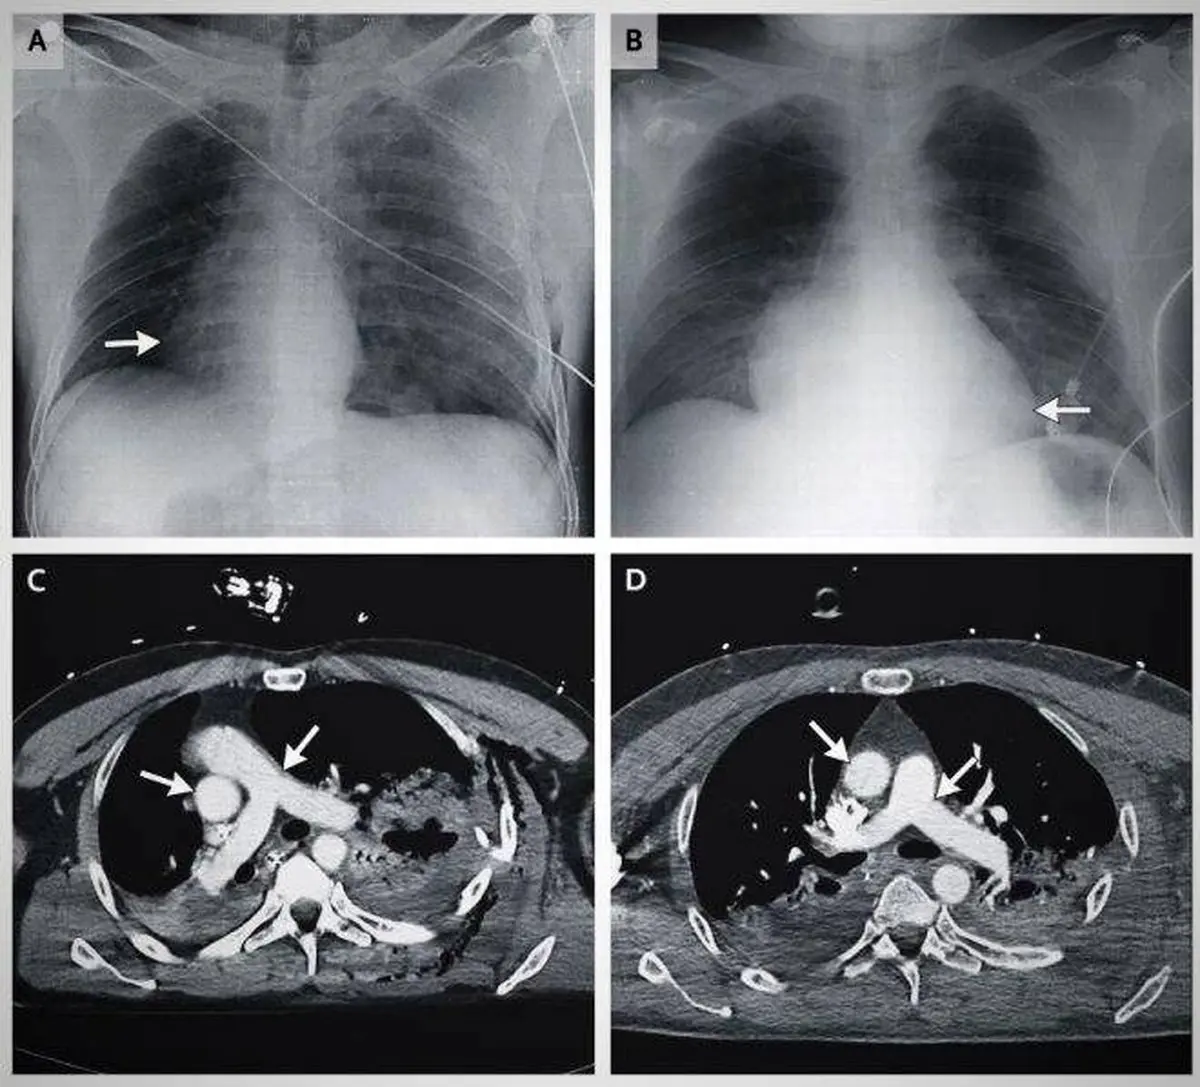

سی تی اسکن ها نشان داد که قلب 90 درجه به سمت راست قفسه سینه رفته است. این مرد 48 ساله که داستان عجیبش را در بخش سرگرمی نمناک می خوانید بر اثر تصادفی در کشور ایتالیا ضربه شدیدی خورده بود که سریع او را به بیمارستان رساندند. زمانی که پزشکان شروع به درمان کردند، متوجه شدند که اتفاق جدیدی در قفسه سینه او رخ داده است. زمانی که خواستند ضربان قلب او را اندازه بگیرند، متوجه شدند قلبش در قسمت راست بدن است و در سمت چپ، هیچ اثری از قلب وجود ندارد. سپس او را برای آزمایش اشعه ایکس و سی تی اسکن آماده کردند. سی تی اسکن هم دقیقا همین موضوع را نشان داد. این گزارش در مجله پزشکی به ثبت رسانده شد. زمانی که اسکن کل بدن انجام شد، متوجه شدند که رگ های بزرگ و اصلی سرخرگ و آئورت، هر دو همراه با قلب به سمت راست رفته اند. این فرد مشکل ریه پیدا کرده بود و چندین شکستگی در دنده هم برایش اتفاق افتاد و به دلیل تصادف، طحال او هم آسیب دیده بود اما با وجود چنین آسیب دیدگی های شدیدی، باز هم زنده مانده بود، هوشیار بود و متوجه اتفاقات اطرافش بود. جا به جا شدن قلب یک مرد بر اثر تصادف! + عکس پزشکان این اتفاق را یک اتفاق بسیار عجیب تلقی کردند که بسیار غیر معمول است و بعضی از آن ها اظهار کردند که تا به حال چنین اتفاقی را به چشم ندیده بودند. چیزی که در مورد این مرد خیلی جالب بود، این بود که قلب او با ظرافت خیلی بالا به سمت راست حرکت کرده بود و او هم کاملاً هوشیار بود و آسیب دیدگی خاصی در بدنش رخ نداده بود.

پزشکان بعد از آزمایشات متعدد متوجه شدند که این اتفاق در حین تصادف رخ نداده است، بلکه چند دقیقه بعد از تصادف قلب این مرد چرخش داشته است. به این صورت که هوا از سمت ریه آسیب دیده به فضای قفسه سینه وارد شده بود و همین هوای بسیار زیاد، قلب را به سمت راست هل داده بود. سپس پزشکان هوای اضافی را از قفسه سینه مرد بیرون کشیدند. جالب است بدانید که بعد از 24 ساعت، قلب این مرد به سر جای اصلی خودش برگشت. آزمایشات نشان داد که قلب این مرد کاملا سالم است و فقط تعداد کمی از رگ های خونی او به دلیل فشار خون حاصل از چرخش، دچار مشکل شده بودند. بعد از این که قلب به جای اصلی خودش برگشت، طحال را طی یک عملیات اورژانسی از بدن مرد خارج کردند. بعد از بیرون آوردن طحال و اصلاح دنده های شکسته، بیمار به طور کامل ریکاوری شد. هیچ علائم و اثری از آسیب دیدگی دائمی به قلب و رگ های خونی او به جای نمانده بود. پزشکان که از این اتفاق بسیار متعجب شده بودند، اظهار کردند که بدن انسان شبیه به یک راز بزرگ است و هنوز هیچ کس به طور کامل ویژگی های منحصر به فرد آن را نمی شناسند.